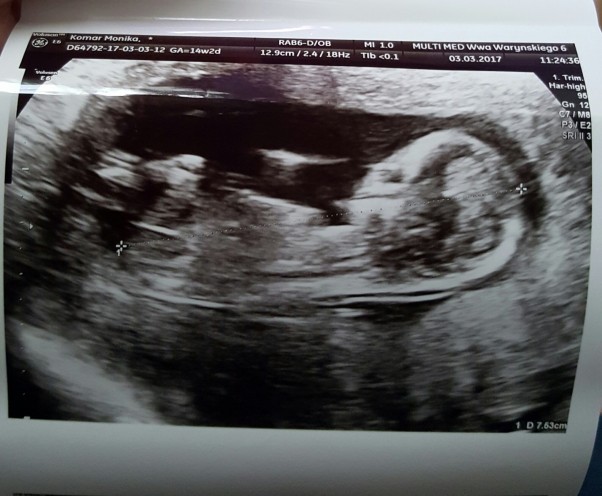

To już ostanie usg w I trymestrze...kolejne będzie tzw.połówkowe a jak na razie moje dziecko urosło do prawie 8 cm. Wiercipieta szalony choć ja jeszcze nie czuje tego ale mam nadzieję że już nie długo...termin porodu już się wyrównał prawie z terminem z om a nie jest już o dwa tygodnie młodszy jak na początku. Czyli wszystko jest w porządku. Płci nie potwierdza pani doktor więc nie wiem czy to Mateusz czy Kornelia ❤❤